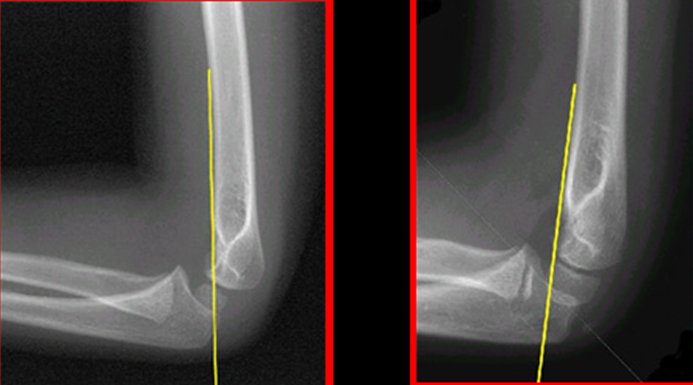

elbow humeral fracture supracondylar forearm capitellum radiographs interpreting intersect

humeral anterior line pediatric fracture abnormal pedia

capitellum dislocation elbow pediatric through drawn lateral anterior humeral pass should line